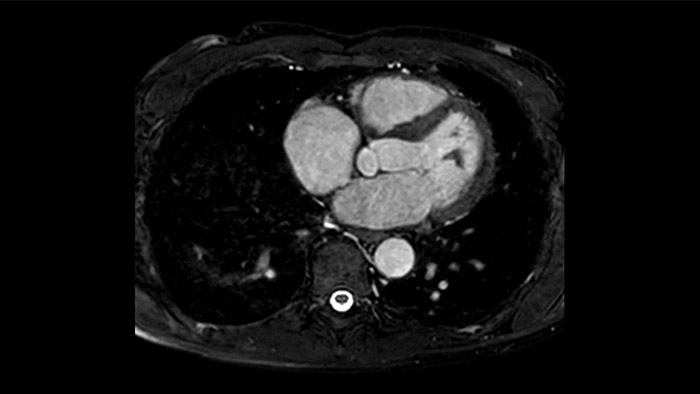

Visualize and evaluate blood flow

Visualise and evaluate blood flow

IntelliSpace Portal MR Caas5,6 4D Flow post-processing solution enables generation of 3D volume reconstructions, to visualise and evaluate blood flow in cardiovascular structures, including heart valves, chambers, and vessels, based on cardiovascular MR 4D Flow imaging.